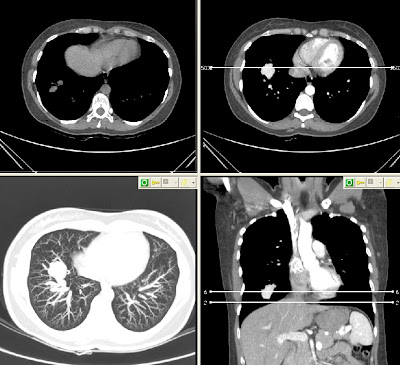

Szerző: admin | okt 30, 2013 | HRCT, Vascular

NECT axial – CECT axial – pulmonary window MIP axial – MIP coronal MIP coronal with the feeding vessels1493672013.09.18.